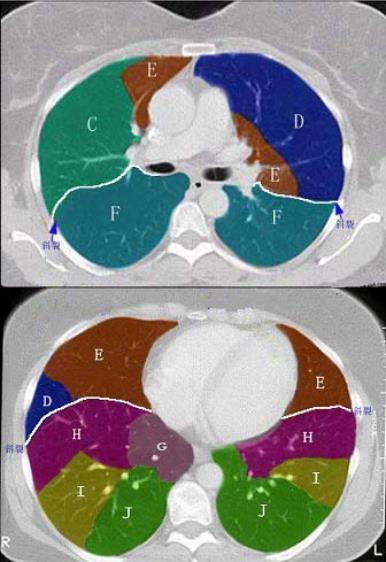

- 单项选择题 结合肺段模式图,选出右肺下叶的组成()。

A、F

B、F+G

C、F+G+H

D、F+G+H+I

E、F+G+H+I+J

- E